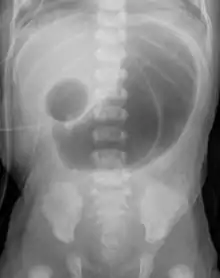

Complication of ileal atresia, meconium peritonitis, in which the bowel perforated before birth. X-ray shows meconium pseudocyst.

If the atresia is not treated, the bowel may become perforated or ischemic. This can lead to abdominal tenderness and meconium peritonitis, which can be fatal.[1]